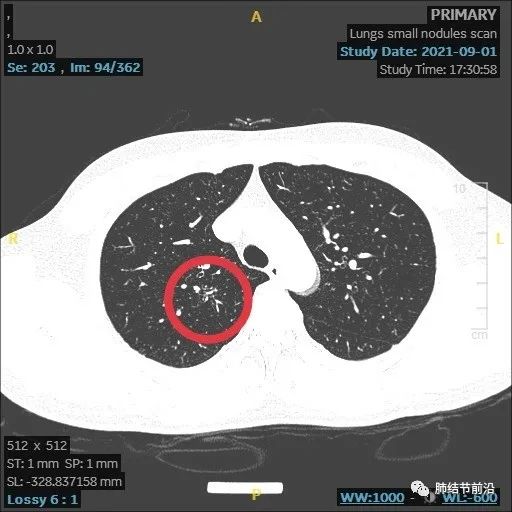

患者之后再复查,果然结节大部分吸收。

本病例显示了炎症性结节的发展过程,由8mm实性结节,变成了14mm的多中心堆积结节,后面又自行吸收。炎症为何种病菌感染,无法肯定,该结节也有结核可能。